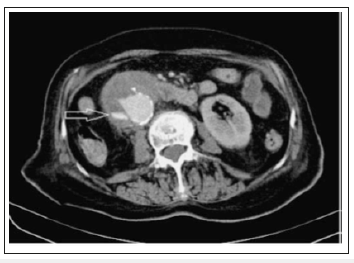

There are many modalities that may aid in the diagnosis of an AEF, but without strong clinical suspicion, these modalities may be futile. The initial evaluation of AEF should be started by esophagogastroduodenoscopy(EGD) to identify the cause of bleeding. The whole duodenum must be investigated in EGD because of the frequent location of the AEF in its 3rd and 4th parts. Findings suggestive of AEF on EGD include visible graft, bleeding, adherent clot, or ulcer or pulsatile mass (Figures 3 & 4). CT scan has 30-61% sensitivity in identifying PAEF, and 90% sensitivity and specificity in identifying SAEF. In addition to identifying the location, it may aid in the identification of an infection or abscess formation if present. Signs found on CT imaging may be gas shadow in or around the graft (sensitivity 40% and specificity 100%), focal wall inflammation and thickening, visible graft (sensitivity 22% and specificity 100%), soft tissue collection around the aorta (specificity 92% and sensitivity 90%), swelling or hematoma around the graft, intravenous contrast within the GI lumen or around the aorta, loss of calcification or tear in the aortic wall (specificity 75% and sensitivity 89%), pseudoaneurysm, and duodenal hematoma (Figures 5 & 6).

Figure 5:CECT: visible true lumen of the aneurysm with extravasation of contrast medium at the level of the second part of the duodenum (arrow).

CT scan has 30-61% sensitivity in identifying PAEF, and 90% sensitivity and specificity in identifying SAEF. In addition to identifying the location, it may aid in the identification of an infection or abscess formation if present. Signs found on CT imaging may be gas shadow in or around the graft (sensitivity 40% and specificity 100%), focal wall inflammation and thickening, visible graft (sensitivity 22% and specificity 100%), soft tissue collection around the aorta (specificity 92% and sensitivity 90%), swelling or hematoma around the graft, intravenous contrast within the GI lumen or around the aorta, loss of calcification or tear in the aortic wall (specificity 75% and sensitivity 89%), pseudoaneurysm, and duodenal hematoma [21-23].